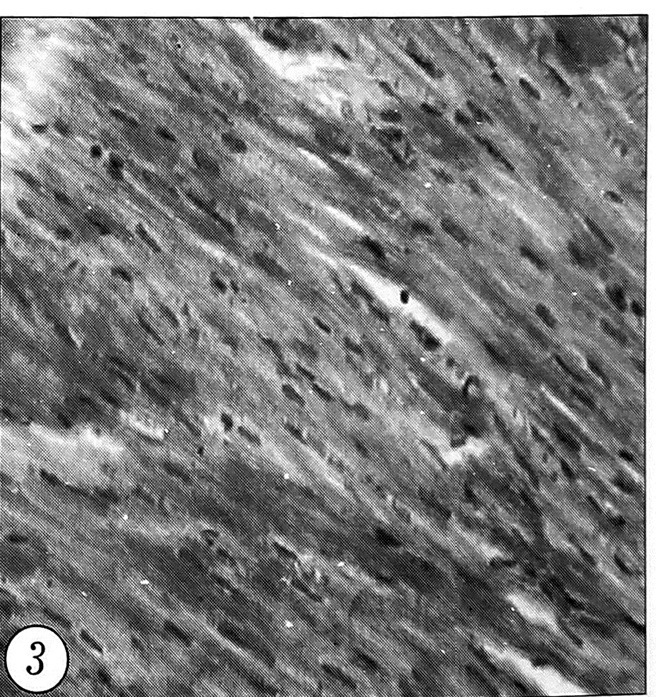

У животных, получавших рексод и мафусол, циркуляторные изменения в миокарде оказались менее выраженными: число и размер субэпикардиальных кровоизлияний у них были меньше. В то же время определялась очаговая зернистость цитоплазмы кардиомиоцитов при отсутствии их поперечной исчерченности (рис. 3).

Рис. 3. Микроскопическая картина миокарда леченого кролика: полнокровие сосудов, отсутствие кровоизлияний, слабо выраженные дистрофические изменения кардиомиоцитов (окраска гематоксилиногл и эозином, ув. 140).